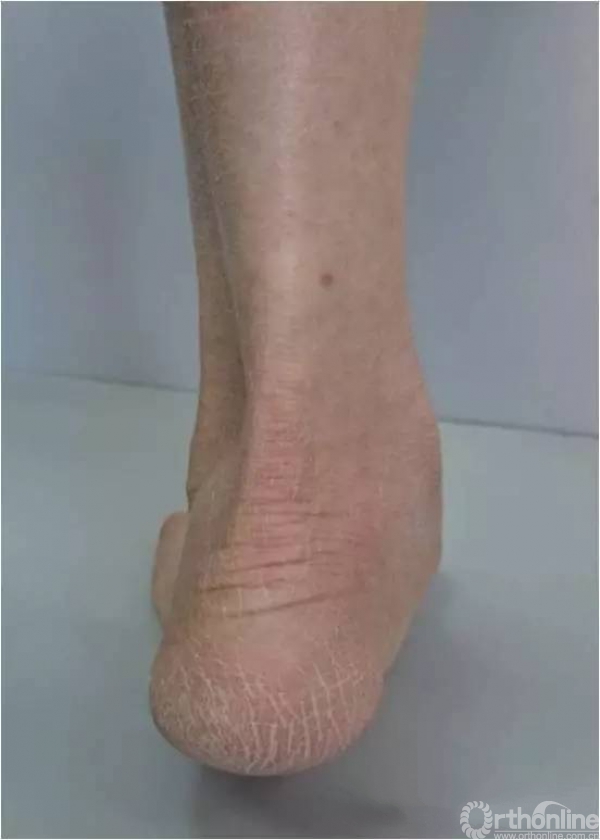

患足外观